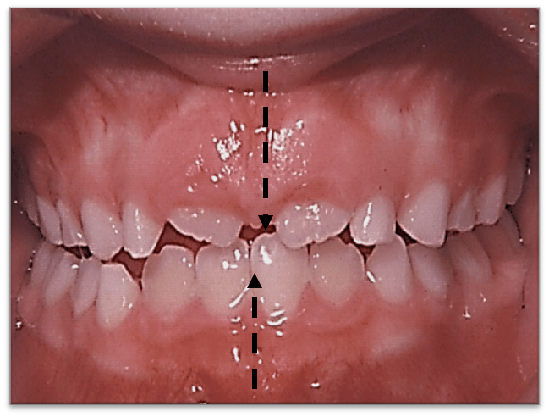

Before

Skeletal Cross Bite

Skeletal cross bites are caused by an under development of the Maxilla. These cross bites often appear to be a unilateral problem. However, on close examination the patient frequently has a skeletal shift of the mandible epsilateral to the cross bite. This in turn means the mandibular condyle on the side of the cross bite is distal to its correct relationship on the articular disk.